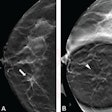

Momentum gathers for DBT plus synthesized mammography